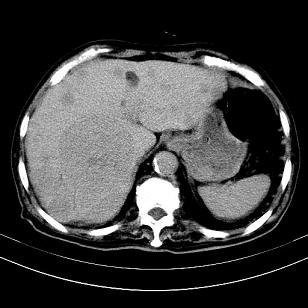

考虑右肝后叶肝癌(部分外生)伴肝内多发性转移

支持肝癌肝内转移,肝硬化。

支持肝右叶巨块型肝癌伴肝内转移.

考虑右肝后叶肝癌(外生型)伴肝内转移。

肝右叶外生性肝癌,伴肝内转移